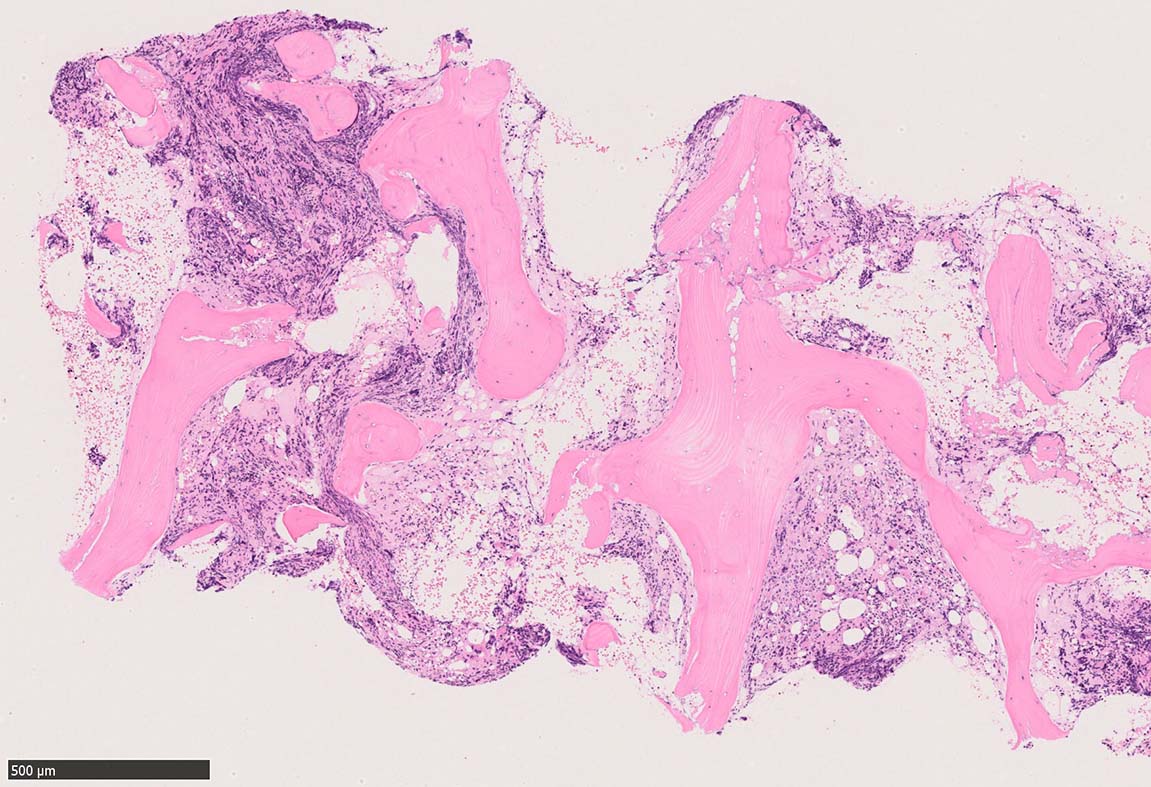

骨髄組織所見 bone marrow biopsy total 6mm in length

塗銀染色

CD42b染色